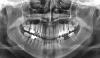

viktoria alekseevna Опубликовано 2 сентября, 2010 Поделиться Опубликовано 2 сентября, 2010 добрый день уважаемые доктора! хочу узнать ваше мнение по поводу моей ситуации. у меня нижняя часть лица достаточно сильно подана вперед что очень портит лицо. но зубы при этом ровные. была у четырех врачей. двое сказали что исправить не получится. одна предложила брекеты без удаления с расширением. другая сказала что без удаления всех четверок выровнять профиль не получится. какое ваше мнение? особенно интересует мнение в варианте с удалением. спасибо за помощ!p.s. на место отсутствующей шестерки буду ставить имплант. Ссылка на комментарий

Премоляр Опубликовано 2 сентября, 2010 Поделиться Опубликовано 2 сентября, 2010 добрый день уважаемые доктора! хочу узнать ваше мнение по поводу моей ситуации. у меня нижняя часть лица достаточно сильно подана вперед что очень портит лицо. но зубы при этом ровные. была у четырех врачей. двое сказали что исправить не получится. одна предложила брекеты без удаления с расширением. другая сказала что без удаления всех четверок выровнять профиль не получится. какое ваше мнение? особенно интересует мнение в варианте с удалением. спасибо за помощ!p.s. на место отсутствующей шестерки буду ставить имплант.Виктория,есть фото зубов в прикусе???По случаю- бимаксиллярная протрузия корректируется именно удалением 4х зубов с целью изменения положения фронт.зубов и ,следовательно, положения губ...тоесть профиль делается немного уплощенным.Но каждый конкр.случай решается индивидуально.Вот по этому и необходимы фото зубов. Ссылка на комментарий

viktoria alekseevna Опубликовано 2 сентября, 2010 Автор Поделиться Опубликовано 2 сентября, 2010 (изменено) Виктория,есть фото зубов в прикусе???По случаю- бимаксиллярная протрузия корректируется именно удалением 4х зубов с целью изменения положения фронт.зубов и ,следовательно, положения губ...тоесть профиль делается немного уплощенным.Но каждый конкр.случай решается индивидуально.Вот по этому и необходимы фото зубов.еще фото:http://www.photoshare.ru/office/image.php?id=5947436http://www.photoshare.ru/office/image.php?id=5947443http://www.photoshare.ru/office/image.php?id=5947478 Изменено 2 сентября, 2010 пользователем viktoria alekseevna Ссылка на комментарий